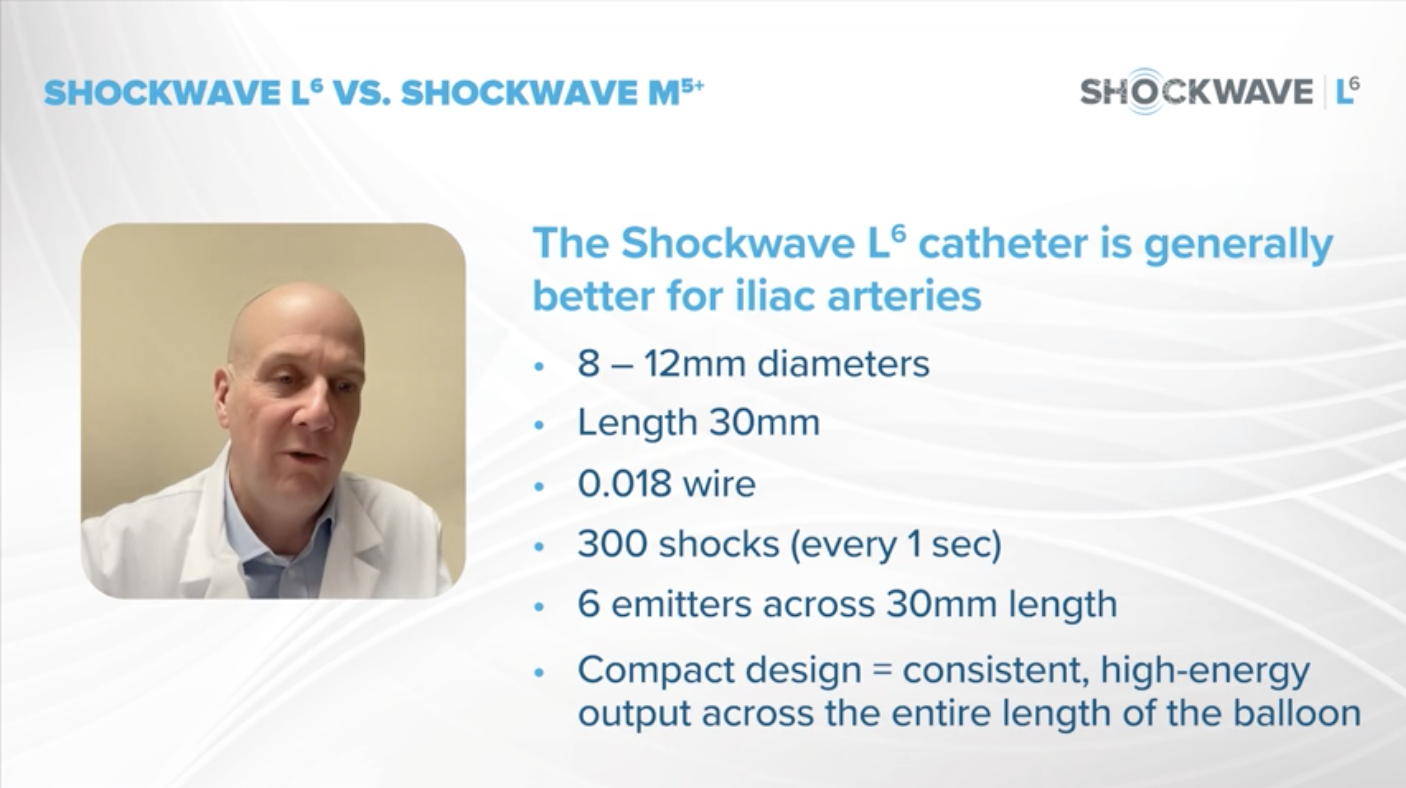

Introducing Shockwave L6 Peripheral IVL Catheter. Now Available in United States and Coming Soon to EU

Introducing Shockwave L6 Peripheral IVL Catheter. Now Available in United States

Dr. Charles Briggs Discusses Shockwave L6 and Its Critical Role in Treating Heavily Calcified Vessels